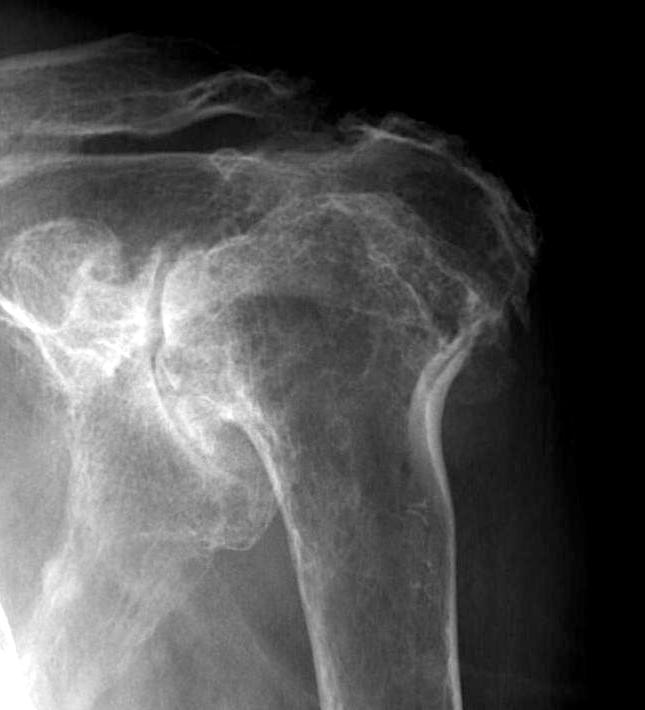

Xray

Typical changes of RA

- regional osteopenia

- marginal erosions and cysts

- humeral head erosions

- medial migration / protrusio